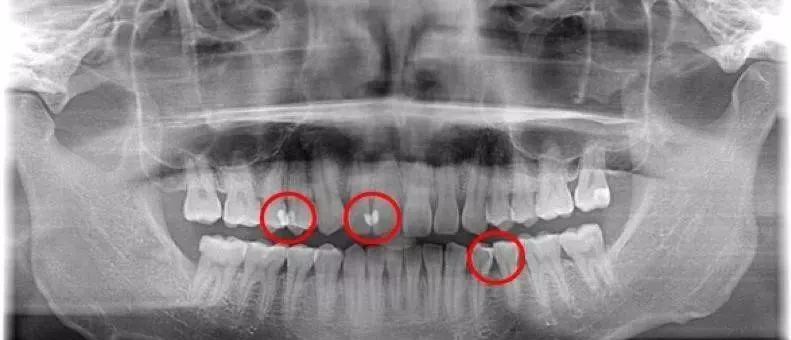

邻面龋由于发生的位置比较隐蔽,所以很难做到早期发现,只有定期到口腔门诊做检查,躺在牙椅上,在充足的灯光下,把牙面吹干,才能看出牙齿边缘是否变色。

有些特殊早期的邻面龋,还需要拍小牙片辅助确诊,所以定期做口腔检查非常有必要的。